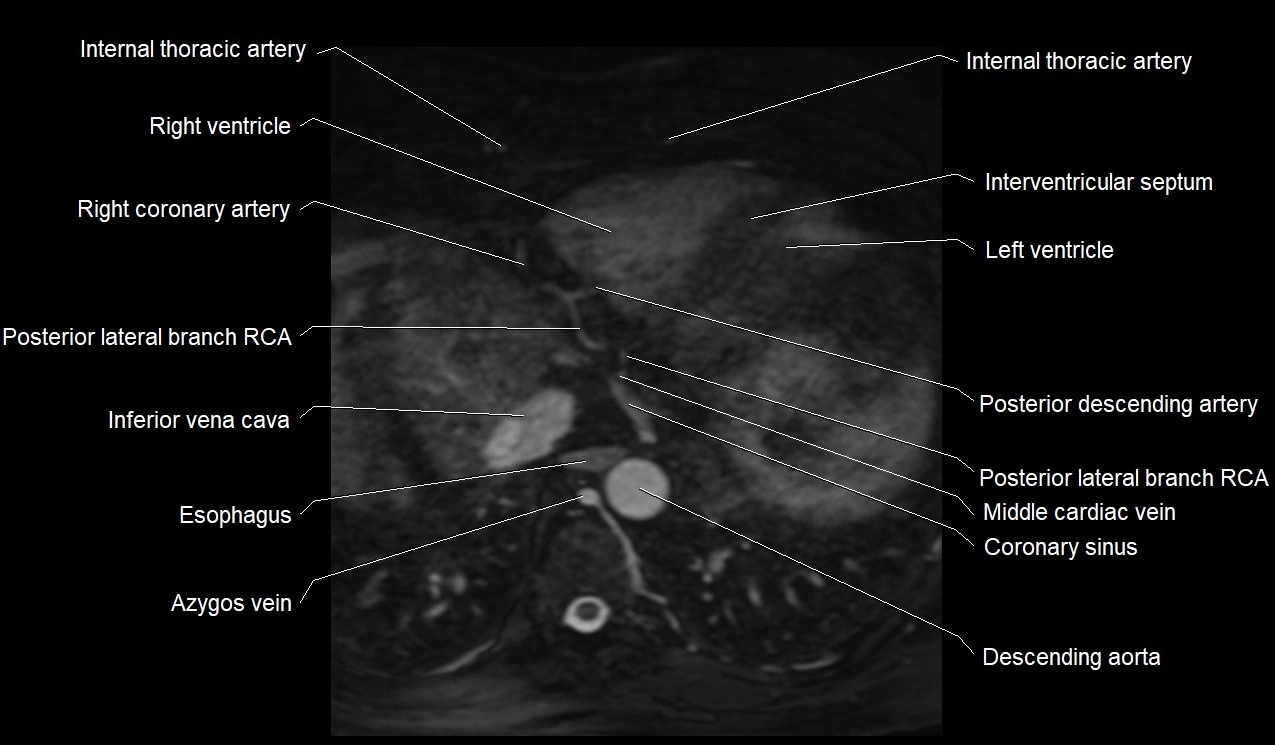

MRI image